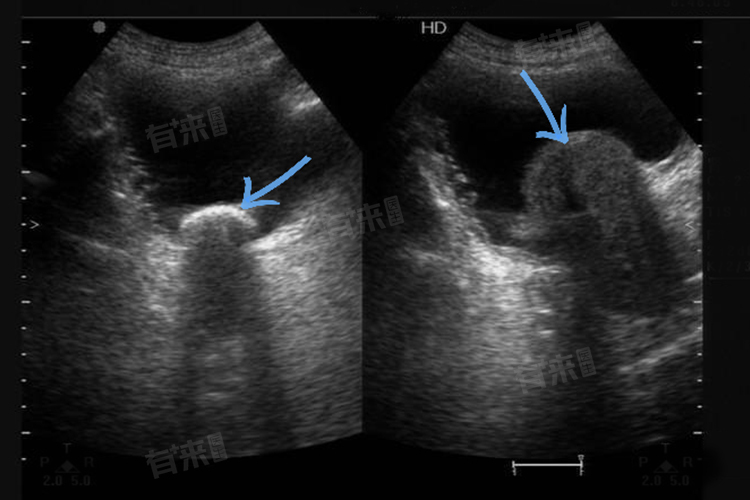

前列腺增生肥大是男性前列腺疾病的一种常见表现,主要发生在老年男性中,随着前列腺体积的增大,会对周围组织和器官产生压迫,导致一系列症状的出现,例如尿频尿急、排尿困难等。

2、排尿困难:前列腺增生肥大会导致尿道管腔变细,排尿阻力增大,从而出现排尿困难的症状,患者可能感到排尿等待时间延长,排尿时费力,尿流变细,甚至出现排尿中断、尿末淋漓、尿不尽等现象,这些症状会随着梗阻的加重而逐渐加重。